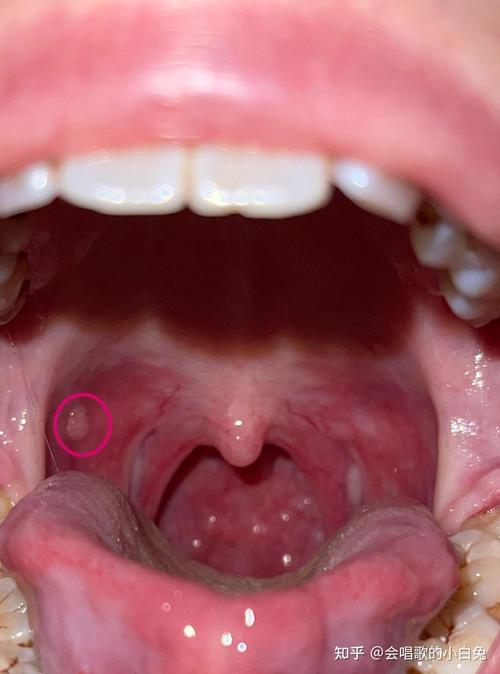

腮帮子内壁长肉凸起是啥原因?

(图片来源网络,侵删)

口腔创伤性血肿或黏液囊肿(最常见)

- 原因:这是最常见的原因,通常是不小心咬到该部位,或者牙齿的尖锐边缘、不良修复的假牙、硬食物(如薯片、坚果壳)反复摩擦刺激,导致黏膜下的毛细血管破裂出血或黏液腺导管堵塞,形成一个充满液体或血液的小囊袋。

- 特点:

- 通常呈圆形、半球形,表面光滑。

- 颜色可能是正常的肉色、淡粉色,也可能是紫色或蓝色(如果里面有血)。

- 初期可能感觉有点胀痛,但很快会变成一个柔软、无痛的包块。

- 大小可能变化,有时会变大,也可能不小心咬破后自行消失,但容易反复发作。